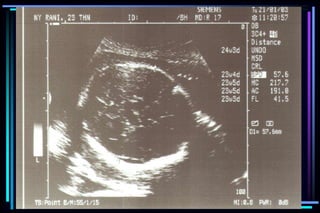

gestational age

 Crown Rump Length (CRL)

 Biparietal diameter (BPD)

 Femur Length (FL)

 Head Circumference (HC)

 Abdominal Circumference (AC)

Accuracy of ultrasound measurement for

different gestational groups

Ultrasound parameter Accuracy

 Gestational sac diameter + 7 days

 Crown Rump Length + 3-5 days

 BPD second trimester + 1 to 1.5 weeks

 BPD third trimester + 2 to 4 weeks

 FL second trimester + 1 to 1.5 weeks

 FL third trimester + 3 to 3.5 weeks

 Multiple parameter (2nd trimester) + 1.5 weeks

 Multiple parameter (3rd trimester) + 2.5 weeks